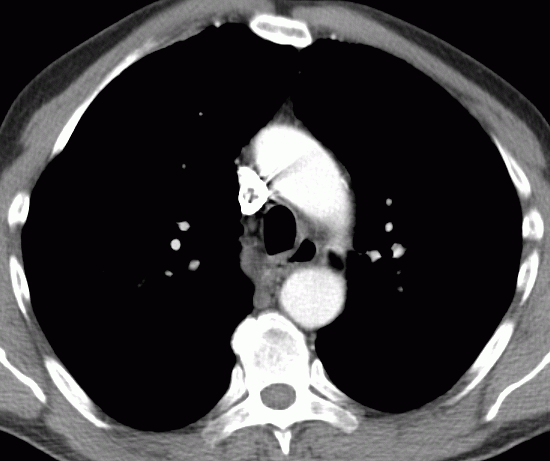

54jähriger Kellner mit einem Oesophagus – Karzinom cT2, welches 2 cm unterhalb der Karina beginnt. Längenausdehnung 6 cm.

Histologie: invasives gering verhornendes Plattenepithelkarzinom, G2.

Klinisch zunehmende Dysphagie.

Das CT zeigt vergrößerte Lymphknoten am Truncus coeliacus (nicht histologisch verifiziert)![]() | ||